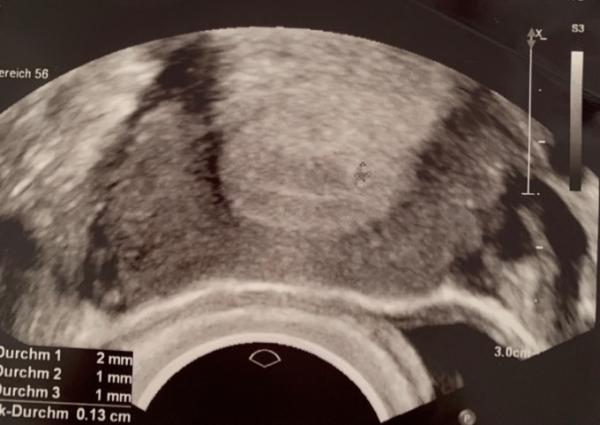

Hallo ihr Lieben, Ich wurde bei 5+0 wegen zwei Fehlgeburten schon zum ersten Ultraschall bestellt. Wie sah euer Ultraschall aus, für diejenigen, die auch so früh beim Ultraschall waren? Gerne mit Fotos

Bild zu Ultraschall bei 5+0 - Schwanger - wer noch? Rund um die Schwangerschaft